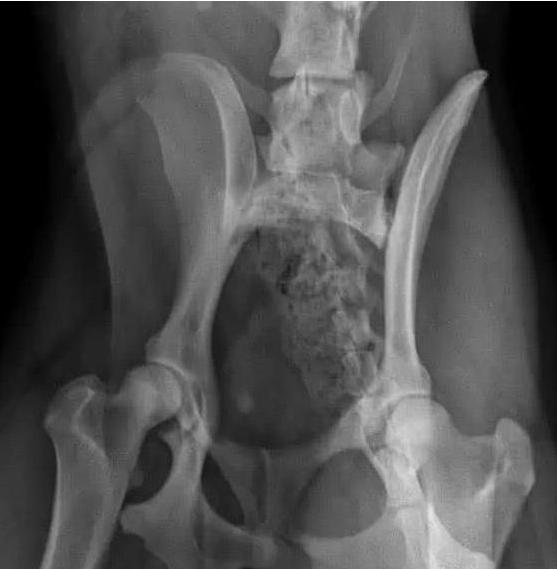

心急火燎的网友也是没办法了,打了一辆车就往宠物医院跑去,经过医生的检查以后,才发现原因竟然是阿拉斯加雪橇犬的体重太胖了,已经超过了正常的阿拉斯加雪橇犬的体型,现在网友的阿拉斯加雪橇犬只能慢慢的动,然后,必须减肥,不然,还会有更多症状出现的。